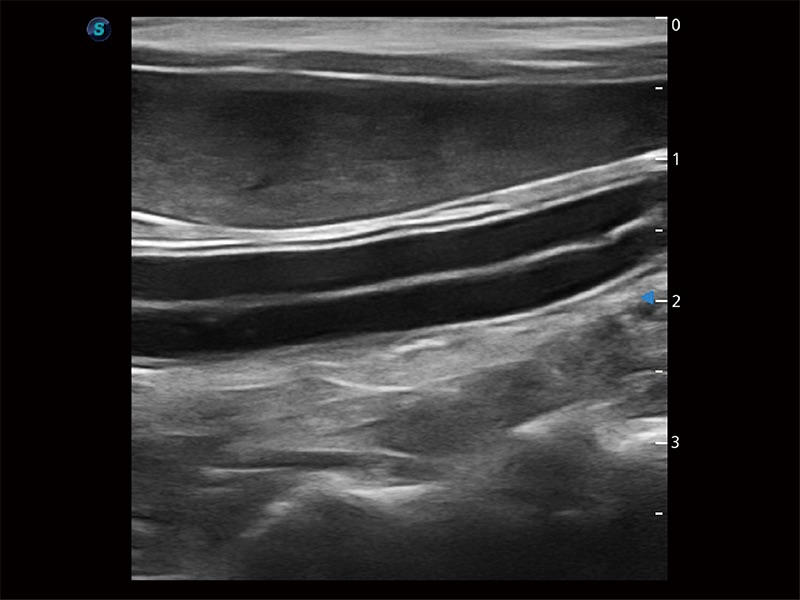

操作简便,无需高频度外力作用即可真实反映组织的形变,快速评估肿瘤良恶性。

为精细结构及组织边缘提供高清晰度的图像和更大的成像视野。帮助减轻医生的用眼疲劳,快速精准获得测量的数据。